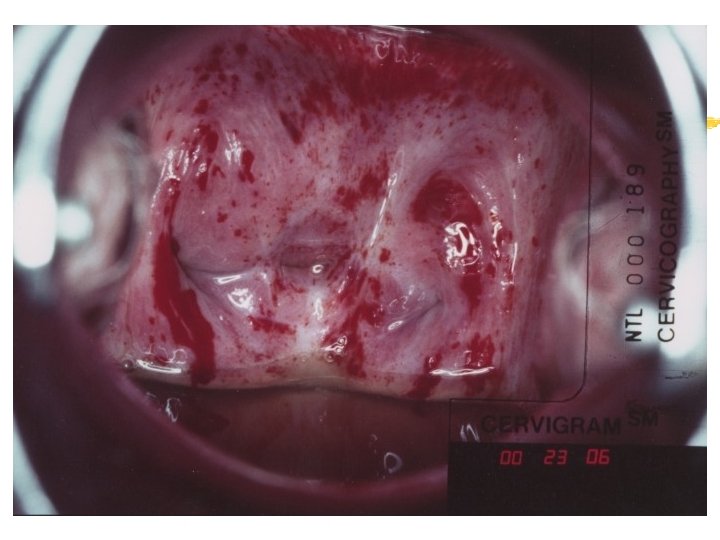

Warning signs of early cervical cancer 1. Yellowish and friable epithelium 2. Abnormal contour 3. Ulceration 4. Atypical vessels 5. Very severe colposcopic atypia 6. Large, significant lesion 7. Canal lesion, going out of range 8. Perimenopausal and post radiation

Atypical transformation zone 1. Acetowhite epithelium 2. Vascular structure a. Mosaic pattern b. Punctation c. Abnormal vessels 3. Leukoplakia

Acetowhiteness 1. SIL …dehydration of nuclear dense lesion 2. HPV …keratin swelling in HPV infected cells 3. Immature squamous metaplasia 4. Healing/regenerating epithelium 5. Congenital transformation zone 6. Inflammation 7. Adednocarcinomas Invasive squamous carcinoma

Vascular structure Mosaic pattern (cobblestone-like appearance). thick whitish areas of small fields polygonal or oval in shape surrounded by reddish borders (fine blood vessels) iodine negative

Vascular structure Punctation … a series of fine red dots on a whitish background. Punctate vessels … dilated, elongated, often slightly twisted and irregular terminal vessels of the hairpin type.